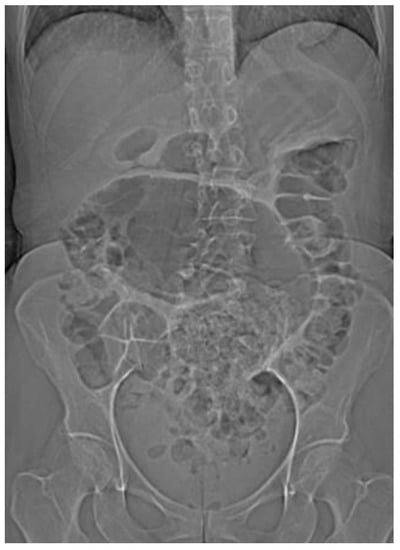

4.4.1. Conventional Radiography

| Abdominal radiograph | 11 (68.75%) | Five patients had CT as the only imaging. |

| Non-specific bowel loops/SBO | 5 (46%) | |

| Classical single loop of large bowel | 6 (54%) | |